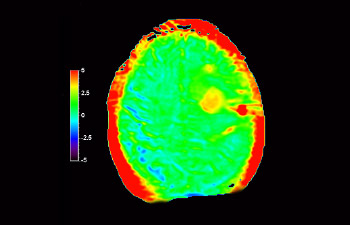

Enhanced diagnostic confidence in neuro oncology